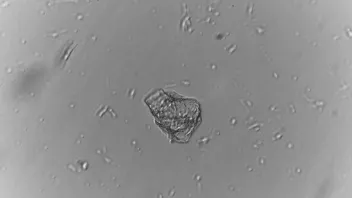

Das Ergebnis war erschreckend.

Ich habe Ihnen einige Bilder davon in den Anhang gelegt, was wir selbst "entdeckt" haben (kein Photoshop oder Fake!!)

Wir haben die Objektträger dann drei Tage liegen gelassen und wieder unter dem Mikroskop angesehen und mussten feststellen, dass sich neue Strukturen gebildet haben und die "alten" sich verändert haben.

Nur im unteren Teil der Ampulle waren diese Partikel vermehrt vorhanden